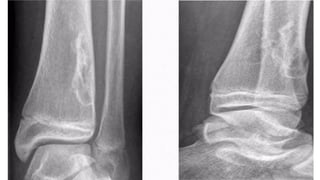

A B C

Plain film features

• An expansile lytic lesion

• S i z e = 2 - 2 0 c m

• Z o n e o f transition - can be ill-defined

• Thin sclerotic margin

• • Cortical breach and soft tissue extension

• CT & MRI

• • To delineate soft tissue extension

• • Shows characteristic fluid-fluid levels (representing areas of

• blood of variable ages)

• ***Other benign lesions with fluid-fluid levels

• • G C T

• • Chondroblastoma